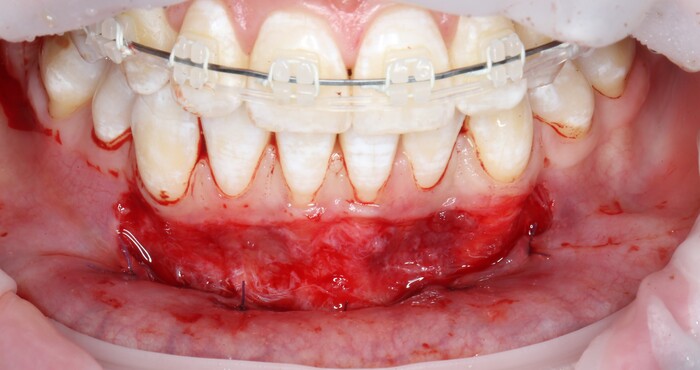

Далее проведена пластика десны, снова два месяца ожиданий и установка временной коронки:

Ну, такое, согласен, но это начало.

Еще через пару месяцев временную коронку сняли для изготовления новой: